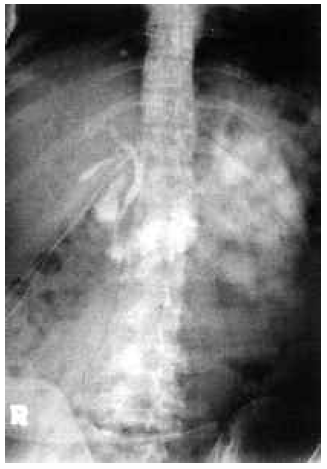

The early postoperative course of the donor was also uneventful. The bilirubin level showed an early rise of up to a total of 11.0 mg and returned to normal after 4 weeks (Table 2). A bile leakage from the cut surface of the liver was detected on the 10th postoperative day, and the bile collection at the left lobe pouch was drained with a percutaneously placed pigtail catheter and, at the same time, a T-tube cholangiography was performed, which showed normal drainage (Figure 7). The bile leakage healed spontaneously without any other access, and, 3 months later, the donor’s condition became completely normal. The liver scan taken during this period (Figure 8) showed a normal hepatotomized liver. At present, the donor is doing very well and working.

Figure 8. Liver scan image showing normal hepatectomized liver.